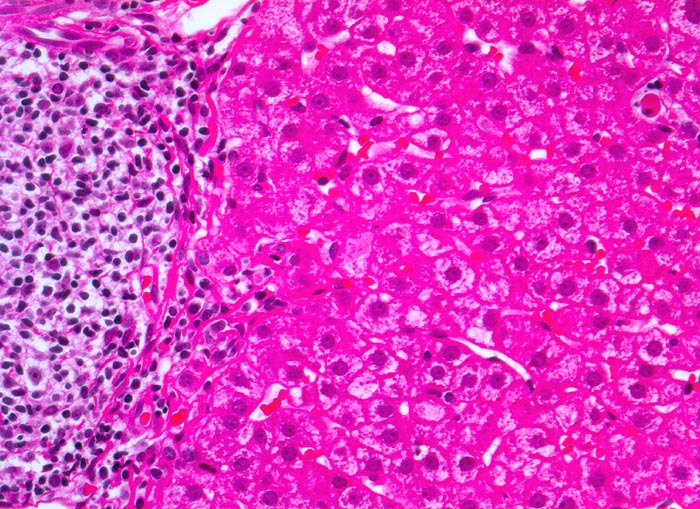

chronische Hepatitis C mit geringgradiger Aktivität

Links im Bild Portalfeld mit starker Vermehrung von mononukleären Zellen. Das Infiltrat greift stellenweise auf das angrenzende Parenchym über (=periportale Hepatitis oder Interface Hepatitis). Das Parenchym ist weitgehend Entzündungsfrei. Es ist eine einzelne Apoptose erkennbar (=Councilman Körperchen oder Einzelzellnekrose).

Fibrose der Portalfelder mit portoportaler Septenbildung.

Das Übergreifen der Entzündung von den Portalfeldern auf das angrenzende Parenchym wurde früher als Piece Meal Nekrose bezeichnet und heute als Interface Hepatitis oder periportale Hepatitis.